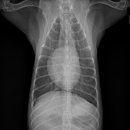

남양주 다산동물병원 24시 고양이건강검진 후기 신장검사 원동물의료센터 경기 남양주시 다산중앙로 15... 24시 동물병원에서 고양이 건강검진을 하고온 후기를 소개해드릴게요. ⏰ 영업시간: 24시 주차 ⭕ 병원...

이후에 병원에서 전화가 와서 아이를 데릴러 오면 되더라고요 특히 담당쌤이 검사결과를 보면서 건강상태와 주의 할점? 등등 자세히 설명해 주셨어요 남양주 다산동물병원 24시 고양이건강검진 베이직 검사...

중증, 만성질환 관리 시스템이 잘 구축되어 있어 장기적으로 꾸준히 관리받기 좋은 병원이라는 느낌을 받았어요. 남양주 다산동물병원 24시 고양이건강검진 원동물의료센터는 단순 검진을 넘어 아이의 삶...

안녕하세요 오늘은 성공적인였던 고양이건강검진을 다녀온후기를 올려봅니다. 저희 집 냥이님이... #남양주동물병원 #24시다산원동물의료센터 #남양주24시동물병원 #다산원동물병원 #다산고양이건강검진...

맛집후기!! 24시 다산 원동물의료센터 #남양주다산동물병원 #남양주다산동물병원24시고양이건강검진... 진행되는 남양주 다산동물병원 24시 고양이건강검진 전문 병원이에요! 여기가 카운터인데 깔끔하고...